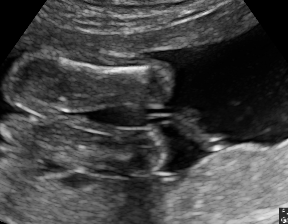

IV-D Experiments on cross-device fetal US

The previous experiment on fetal US images is supported by data restricted to one US imaging device. Here, we evaluate MIDNet for a standard plane classification task on data from different imaging devices (different device domains). Device A is “GE Voluson E8” which is the same device in Sec. IV-C, which acquired 2D fetal US images. Device B is “Philips EPIQ V7 G” which acquired another images sampled from about 500 2D US examinations with gestational ages between 20-32 weeks (see Fig. 2 (b)). In this experiment, we use four different anatomical standard plane locations with sufficient images in both domains, including Abdominal, Brain, Femur and Lips, which are selected by an 10-year-experienced sonographer. In this experiment, the source domain is set as device A while the target domain is device B. Training data consists of all four standard planes from the source domain as well as Abdominal and Brain from the target domain. We aim to separate anatomical features (categorical features) and imaging device features (domain features) to obtain generalized anatomical features for achieving high performance of standard plane classification on (Femur and Lips). Here, contains Abdominal, Brain, Femur and Lips from the source domain and contains Abdominal and Brain from the target domain. Hyper-parameters to in Eq. 11 are for the proposed MIDNet model and is additionally for MIDNet+.

The classification performance of baselines and the proposed model are shown in Table. III. We observe that MIDNet outperforms the state-of-the-art on on the most important test data for average F1-score and recall. Among all the models in the ablation study, MIDNet+ achieves the best performance on and , demonstrating that metric learning contributes to the separation of seen categories in both domains. MIDNet outperforms MIDNet w/o , MIDNet w/o and MIDNet w/o on , illustrating the importance of all proposed components in MIDNet for the classification of unseen categories in the target domain. In addition, Fig. 7 (b) shows the effectiveness of mutual information disentanglement () to learn domain-invariant categorical features.

The confusion matrices in Fig. 8(b) show the effectiveness of unlabeled data in the proposed method. The classification accuracy of Femur and Lips in MIDNet improves when using unlabeled data.

From Fig. 9 (b), we observe that classification performance improves with the increase of labeled data in most cases. However, the performance reaches its peak after a certain percentage of labeled data is added. For example, the peak point is in this experiment.

In addition, we utilize t-SNE plots for feature visualization in Fig. 10. Comparing Fig. 10 (a) and Fig. 10 (b), we observe that with mutual information disentanglement, (1) samples from the same category are more tightly clustered (see the top row) and (2) the source domain and the target domain are overlap more (see the bottom row). This indicates that mutual information disentanglement is important for learning categorical-focused and domain-invariant features. Fig. 10 (a), (c)-(d) show that the proposed method outperforms other state-of-the-art methods for learning category-discriminative and domain-invariant features, especially for unseen categories in the target domain (e.g., (a) vs. (d)).

We further present correctly classified and mis-classified examples of using MIDNet in Fig. 11 (b).